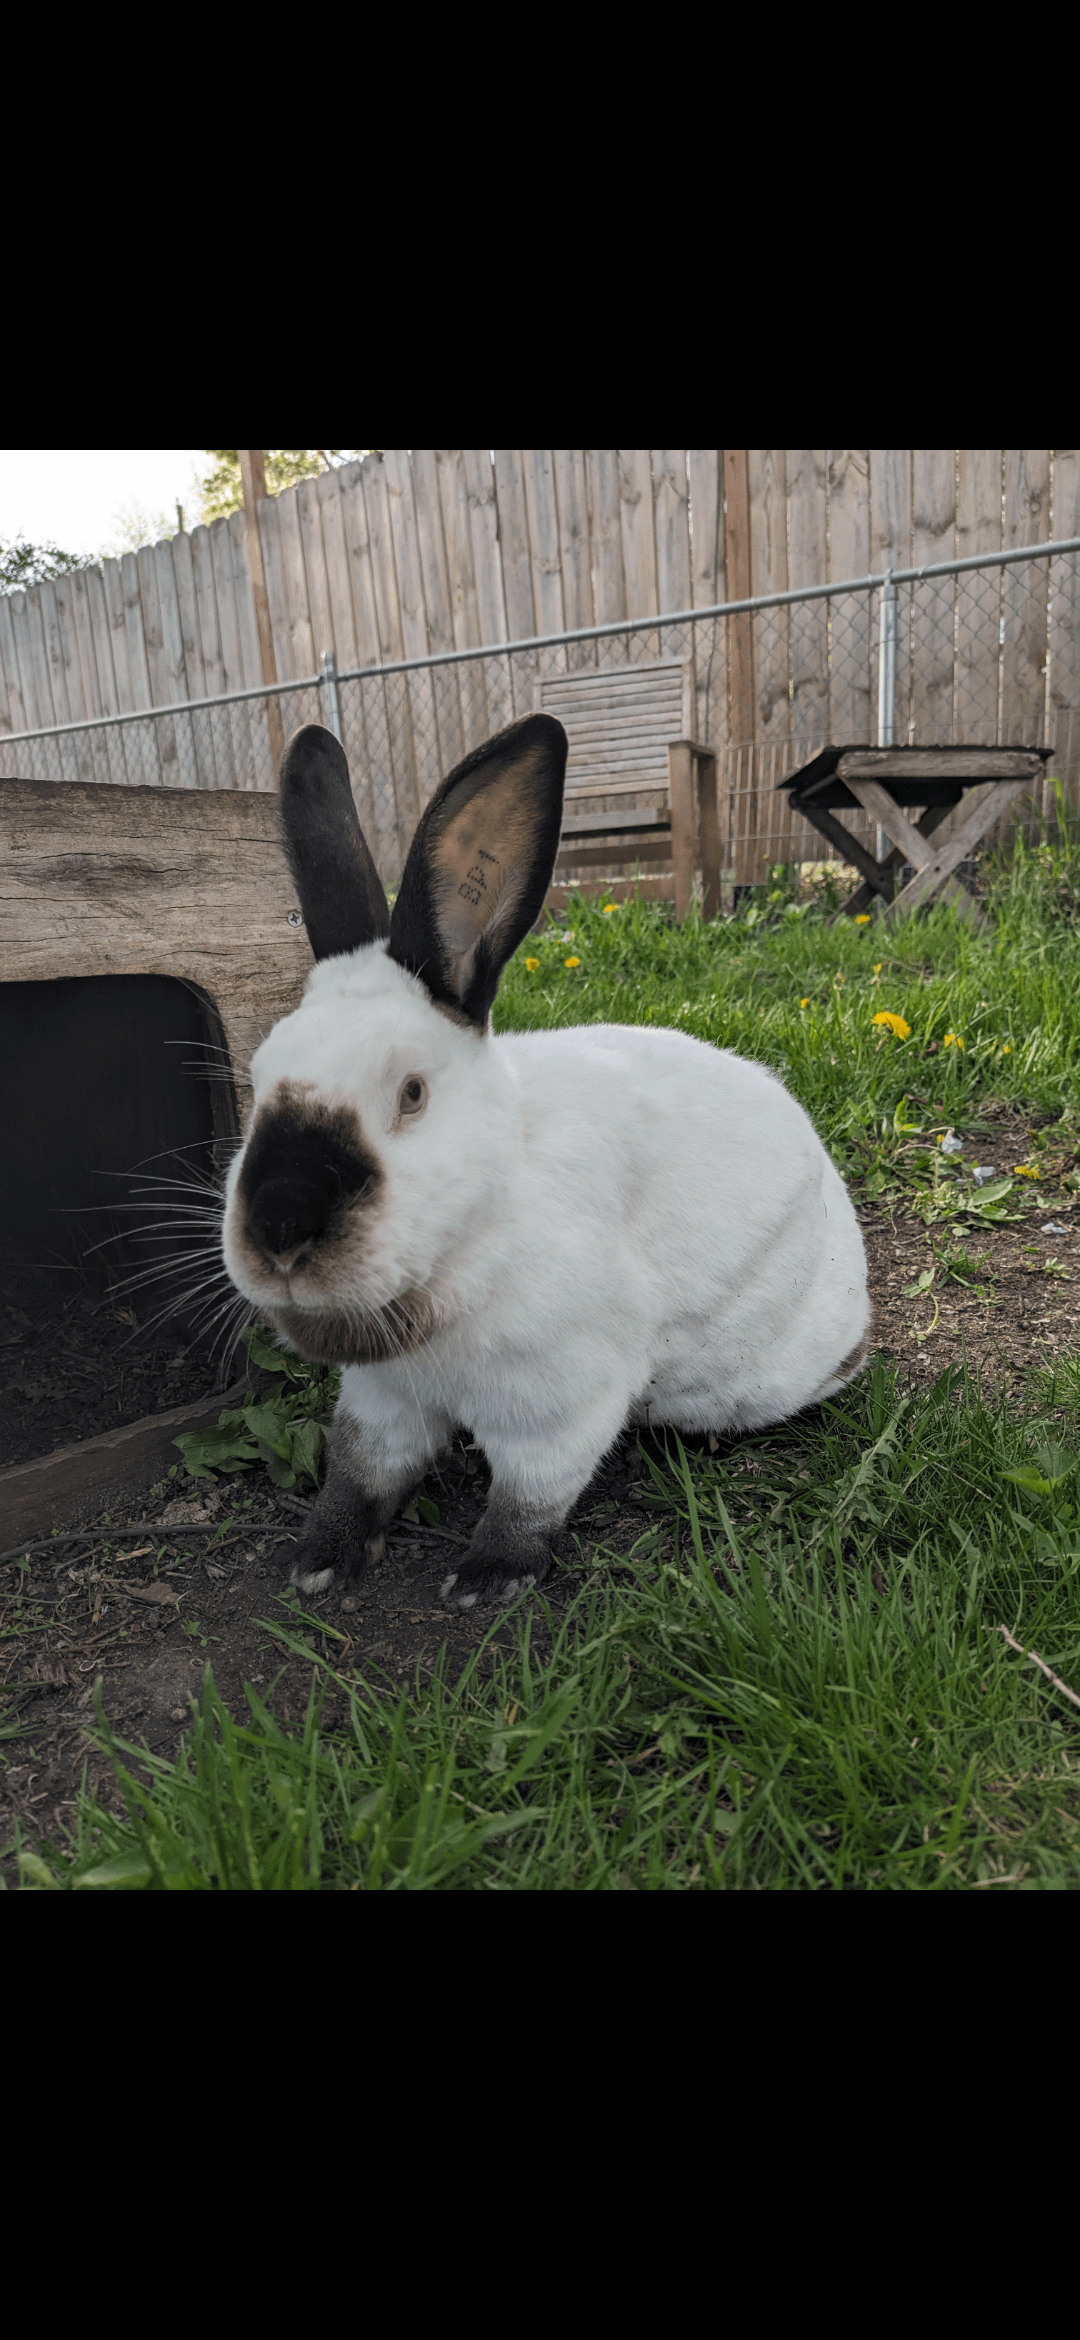

Yesterday morning, I noticed my rabbit Harry was limping on one front paw. He was acting completely normal otherwise, in fact was eating like a champ and running around like nothing was wrong! I called my normal vet and made an appointment for Friday and gave him some metacam I had on hand. This morning, as I was examining him more, I noticed what felt like his shoulder dislocated. I immediately brought him to the ER vet. I was thinking they would either tell me it was a sprain or a dislocation that they could easily fix but no. They told me he has bone cancer and a severe fracture to his upper arm. She told me the only options were amputation, which she didn't recommend because she said the cancer is showing beginning stages of spreading to his lungs and even if that weren't the case, she would be very hesitant due to his age. I am beside myself. I had no idea when I went in that I would be making arrangements to say goodbye to my favorite rabbit child. I brought him home to keep him comfortable for a couple days (lots of pets and metacam) and I am keeping my appointment for Friday but now it is for euthanasia. He's been coming out of his sedation for the X-ray over the last couple hours and still has such a strong appetite! Even the hospital staff were shocked at how injured he is with his appetite and demeanor. He is a trooper and I am devastated that I have to say goodbye to him. I rescued him from a free Craigslist ad in 2017. He was bred through 4H, won some kid a bunch of blue ribbons and then was discarded like trash. He was also living outside in a wire bottom cage in the harsh Minnesota winter. I know I gave him the best life I possibly could and a long one at that but it is incredibly difficult saying goodbye to them despite these facts. Apparently this bone cancer is very rare in rabbits but tends to happen more in older age. So as much as I'm sharing this to vent, I also am sharing to educate. If your rabbit is limping for any reason, please bring them in and get an X-ray.